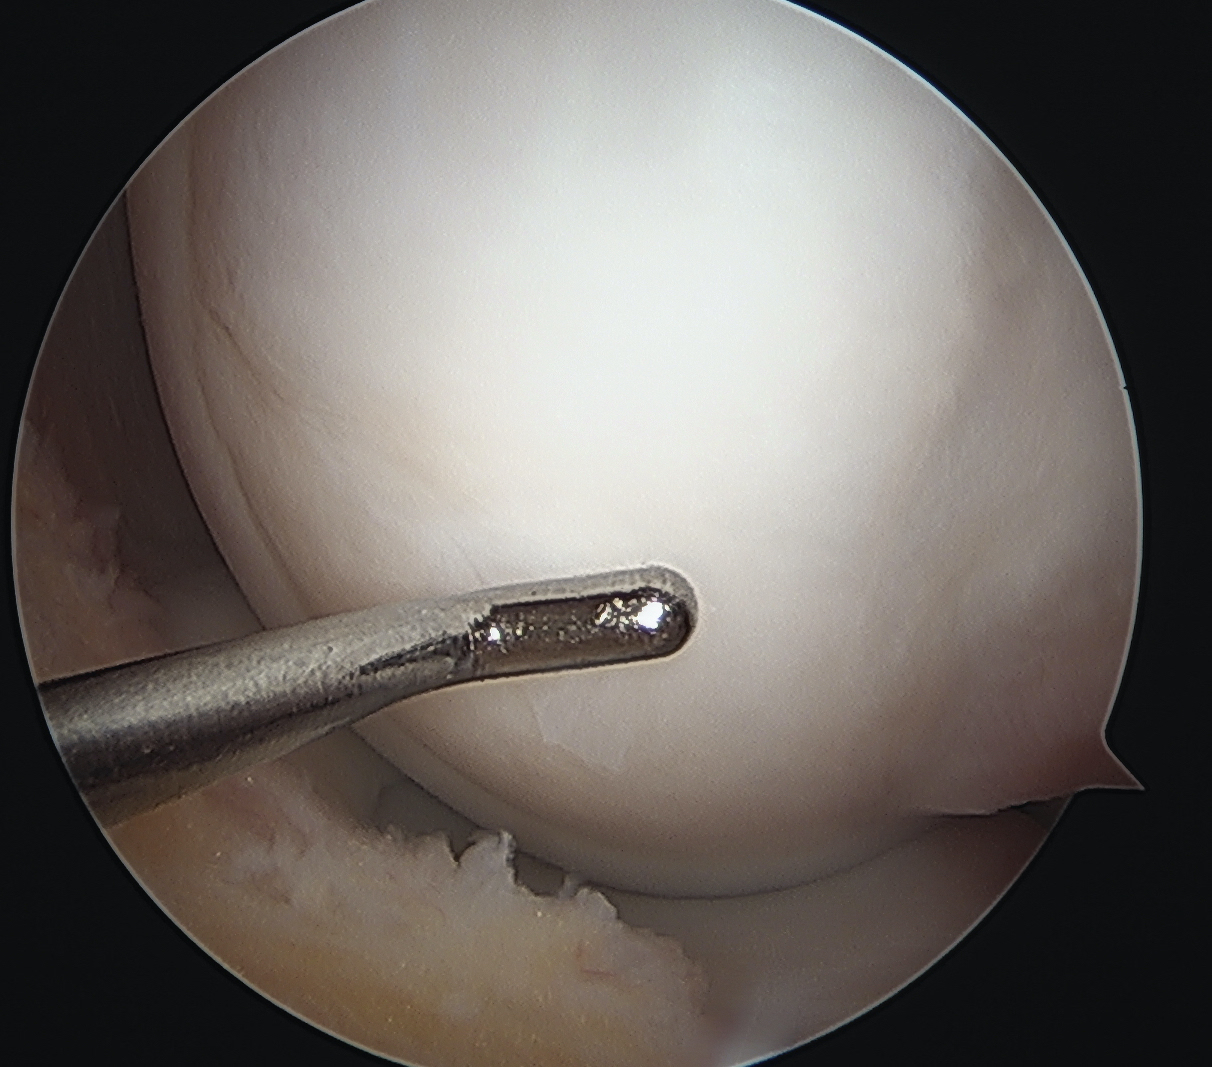

Arthroscope in lateral portal

Clear fat pad

Ensure can see entire dimensions of OCD

If fragment is displaced, reduce and pin with accessory K wire

Instrument and screw from accessory medial portal

- fragment is lateral aspect of the MFC

- typically need trans patella tendon portal to ensure correct trajectory

- ensure K wires centered in fragment